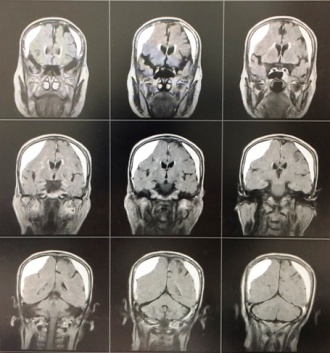

頭部MRIの検査で.....

早速 頭部MRIの検査をしたところ、慢性硬膜下血腫を認めました。